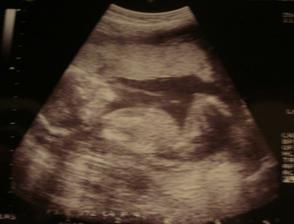

* 5. 11. poradna, 19 tt a mimi se má čile k světu. Pravděpodobně už víme, co nosim v bříšku...